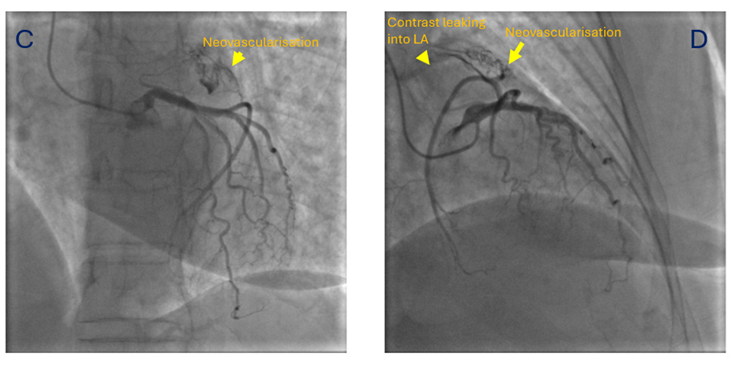

She was taken up for a preoperative coronary angiography with a plan for a subsequent mechanical mitral valve replacement. The coronary angiogram revealed normal epicardial coronary arteries. However, the atrial branch of the left circumflex artery was seen giving small branches to a left atrial appendage (LAA) clot (neovascularization), with contrast leaking into the left atrium (LA) from these neovessels (Figure, Video). A transesophageal echocardiogram later confirmed the LAA clot. The patient was subsequently planned for a mechanical mitral valve replacement and LAA clot removal.

In a previous study from our center, which included 81 patients with rheumatic mitral stenosis, angiography predicted thrombosis by demonstrating neovascularity, manifesting as a bunch of small vessels arising from the circumflex branch of the left coronary artery and terminating in a network of smaller vascular channels, with a blush of contrast medium consolidating into small lakes.1 For recognizing thrombi in the LA or LAA, selective left coronary angiogram demonstrated sensitivity and specificity of 72.7% and 92.7%, respectively, and an 88.8% predictive value.1